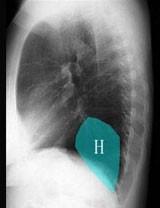

问题 在图所示正常胸部X线影像图像上,该英文字母所代表的肺段为 ( )

选项 A、H代表后基底段 B、H代表背段 C、H代表前基底段 D、H代表外基底段 E、H代表内基底段

答案 D